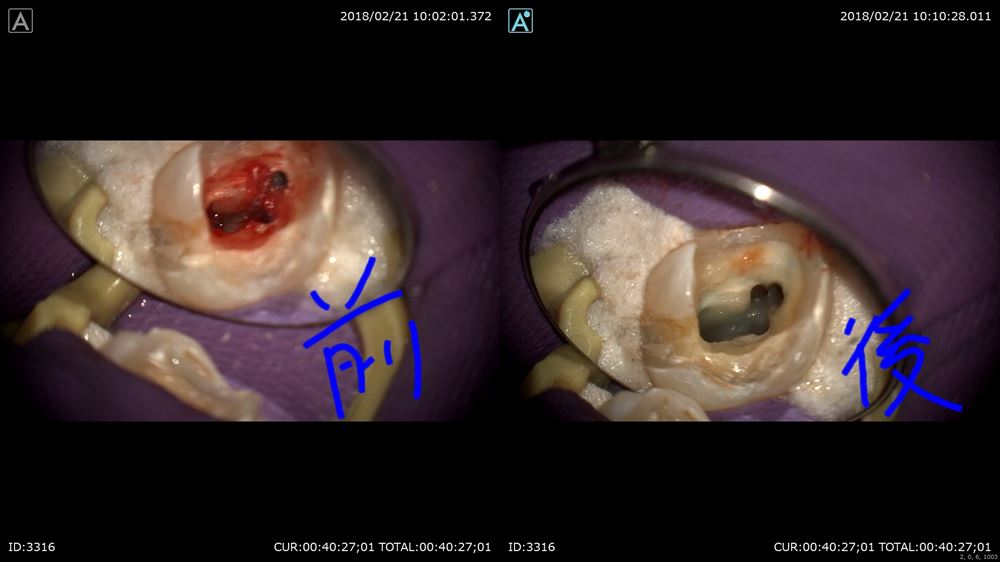

神経が腫れて辛そうでした。歯科ドックで原因をお話しし本日精密根管治療スタート

この歯。やはり銀歯虫歯からの細菌侵入。隙間がありますね。

アップ。こんなに。。。

金属を外すと

神経が腫れていました

無痛で行います。

4根見つけて

綺麗になりました。

術前と術後

これで痛みがなくなります。良かったです!!